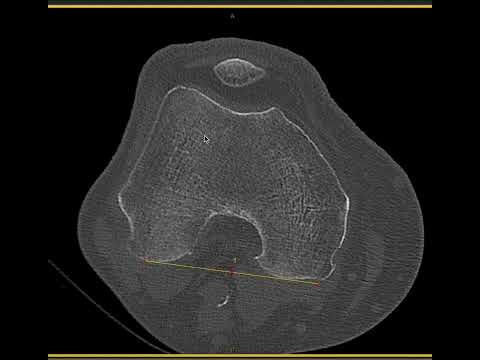

VARUS KNEE IN 61M

How would you manage this #orthotwitter?

Vote on this case for CME: orthobullets.tiny.us/m7wjdzp